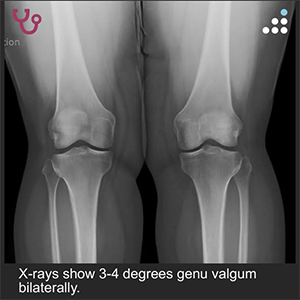

PE: On physical exam, the patient has 3-4 degrees valgus bilaterally. There is a mild effusion about the left knee. ROM of the left knee is 0-130 degrees. There is a normal drawer, pivot shift, and Lachman’s test.